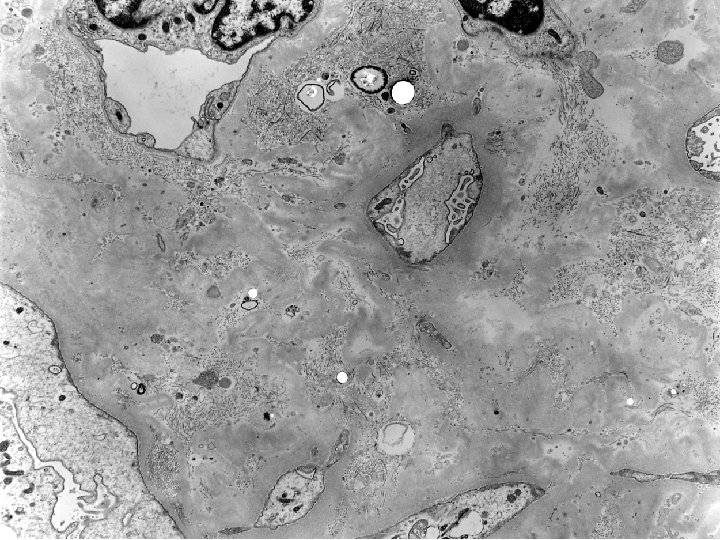

Diagnosis Renal Biopsy: • Essentially end stage kidney with nearly complete glomerulosclerosis but with

Diagnosis Renal Biopsy: • Essentially end stage kidney with nearly complete glomerulosclerosis but with clear cut intimal arteritis in one large artery. Probable acute vascular rejection superimposed on some previous process which led to the glomerulosclerosis. • Rule out pyelonephritis • Peritubular capillary basement membrane multilayering. • G 0 CG 0 I 2 CI 3 T 0 CT 3 V 1 CV 2 AH 0 MM 0